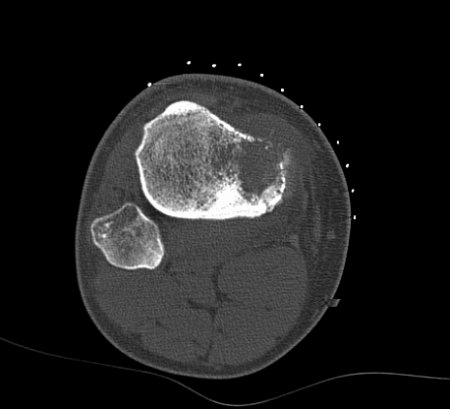

Osteossarcoma

Tomografia computadorizada (TC), incidência axial; osteossarcoma da tíbia proximal; produção de matriz e destruição óssea são mais bem visualizadas em tomografias convencionais

Do acervo do Dr. Michael J. Klein e da Dra. Luminita Rezeanu